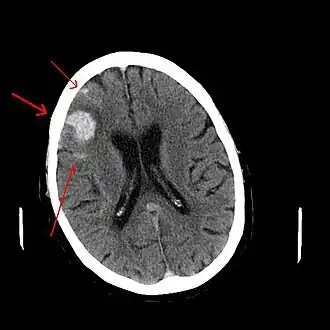

CT scan van een spontaan intracerebraal hematoom

Intracerebraal hematoom

Intracerebraal hematoom is de medische aanduiding van een bloeding, waarbij het bloed zich in het hersenweefsel bevindt. Dit is de meest voorkomende hersenbloeding en deze treedt spontaan op. De gevolgen voor de patiënt zijn ongeveer hetzelfde als bij een herseninfarct. De belangrijkste oorzaak is hoge bloeddruk, dus hypertensie. Dit is de enige vorm die een echte 'hersenbloeding' mag heten.